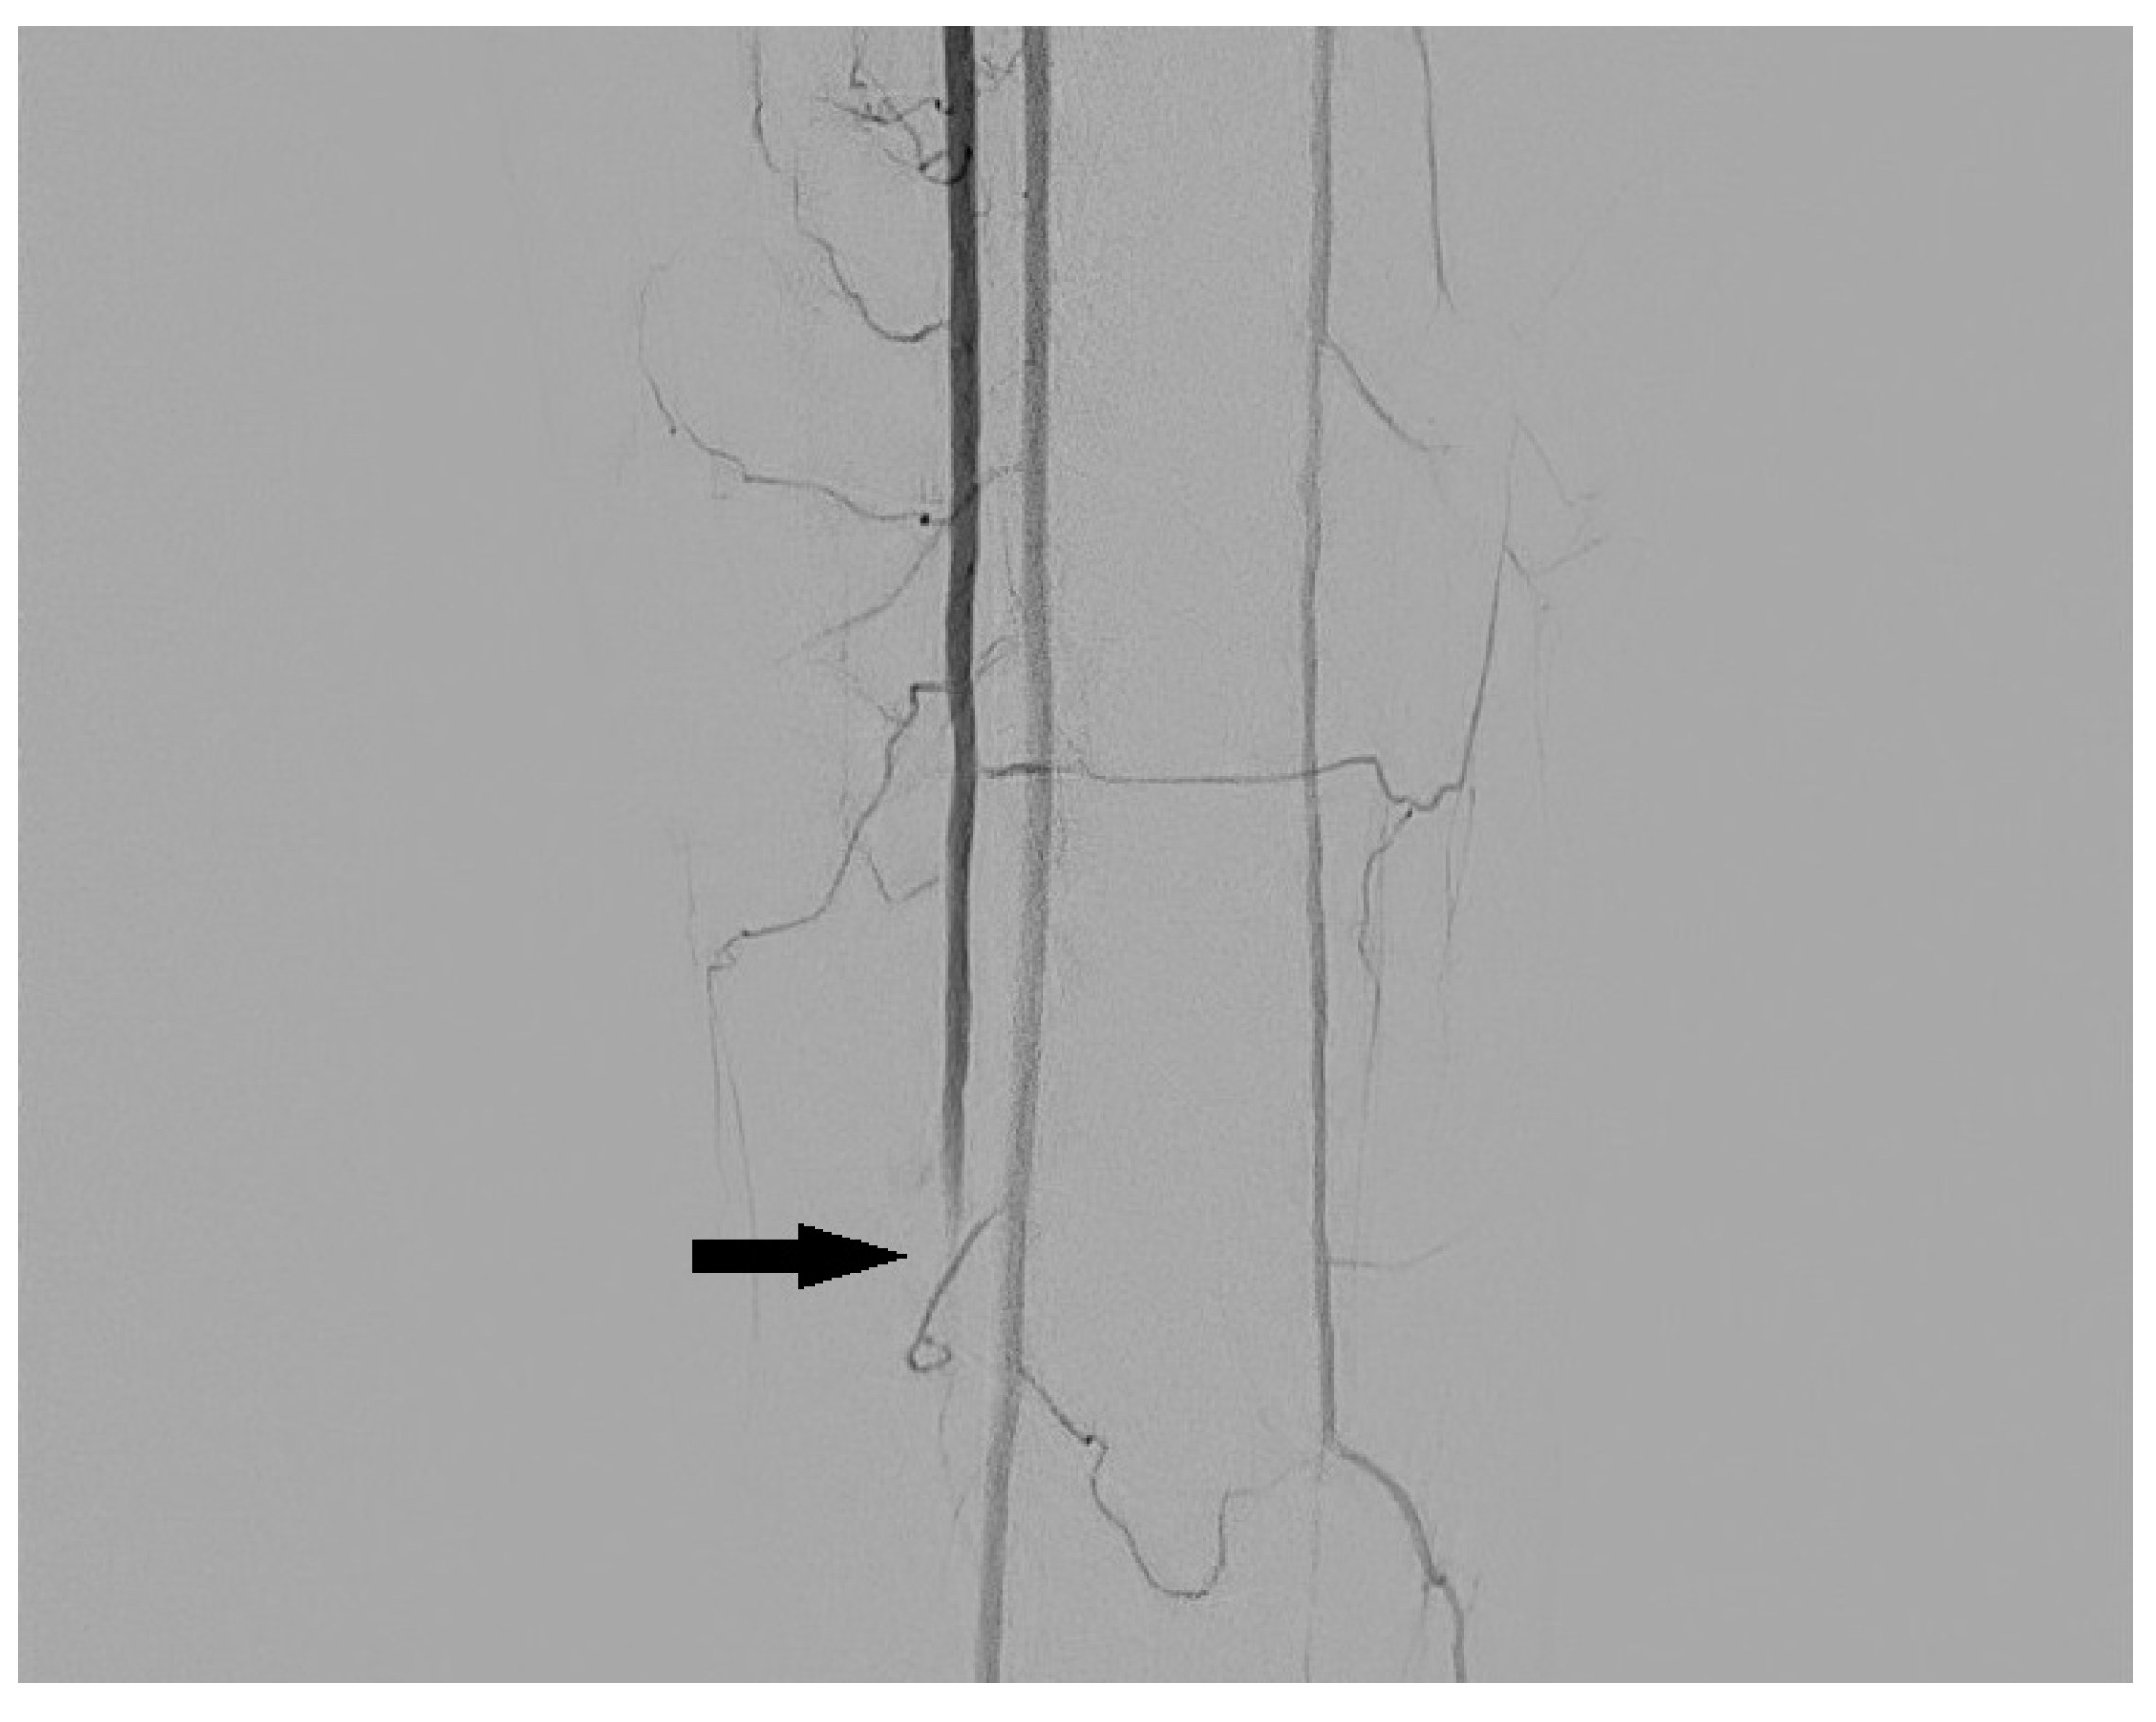

3.2. Dissection